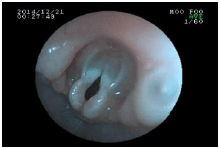

内視鏡を使った呼吸器の検査

内視鏡は胃腸以外にも、喉や気管などの呼吸器の検査・処置にも使われます。

![]() 気管の中 |